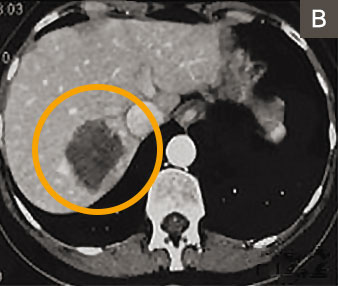

Abb 4a E 55 Jahriger Patient Mit Lebermetastasen Eines Kolorektalen Download Scientific Diagram